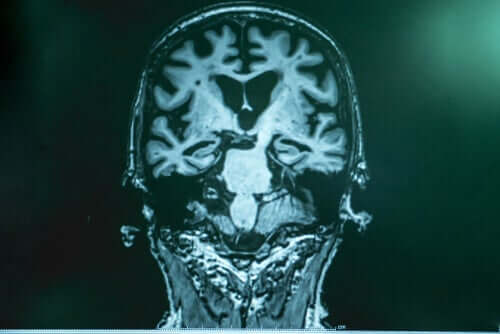

Lopera on selvittänyt, että Alzheimerin taudissa aivoihin kertyy eräänlaista “roskaa”. Tämä roska koostuu proteiinista, jota kutsutaan amyloidiksi. Sen fragmentit taas yhdistyvät keskenään ja muodostavat jotain “tahmaisen” kaltaista, joka tarttuu neuroneihin ja johtaa merkittävään “virheiden vesiputoukseen”. Toista tämän roskan osaa Lopera kutsuu tauksi, joka ympäröi neuronin, lukitsee sen sisälleen ja tappaa sen. Tau on näistä kaikkein vaarallisin.

Perusteellisten tutkimusten jälkeen Bostonissa asiantuntijat havaitsivat, että potilaan aivot olivat täynnä amyloidia, ja tämä määrä oli jopa merkittävämpi kuin muissa tapauksissa. Tätä vastoin potilaan aivoista löytyi kuitenkin vain vähän tauta. Tutkimukset antoivat tutkijaryhmälle mahdollisuuden varmistaa, että tällä potilaalla oli toinen mutaatio, joka inhiboi taun tuotantoa ja hidasti näin ollen myös kyseisen taudin etenemistä.